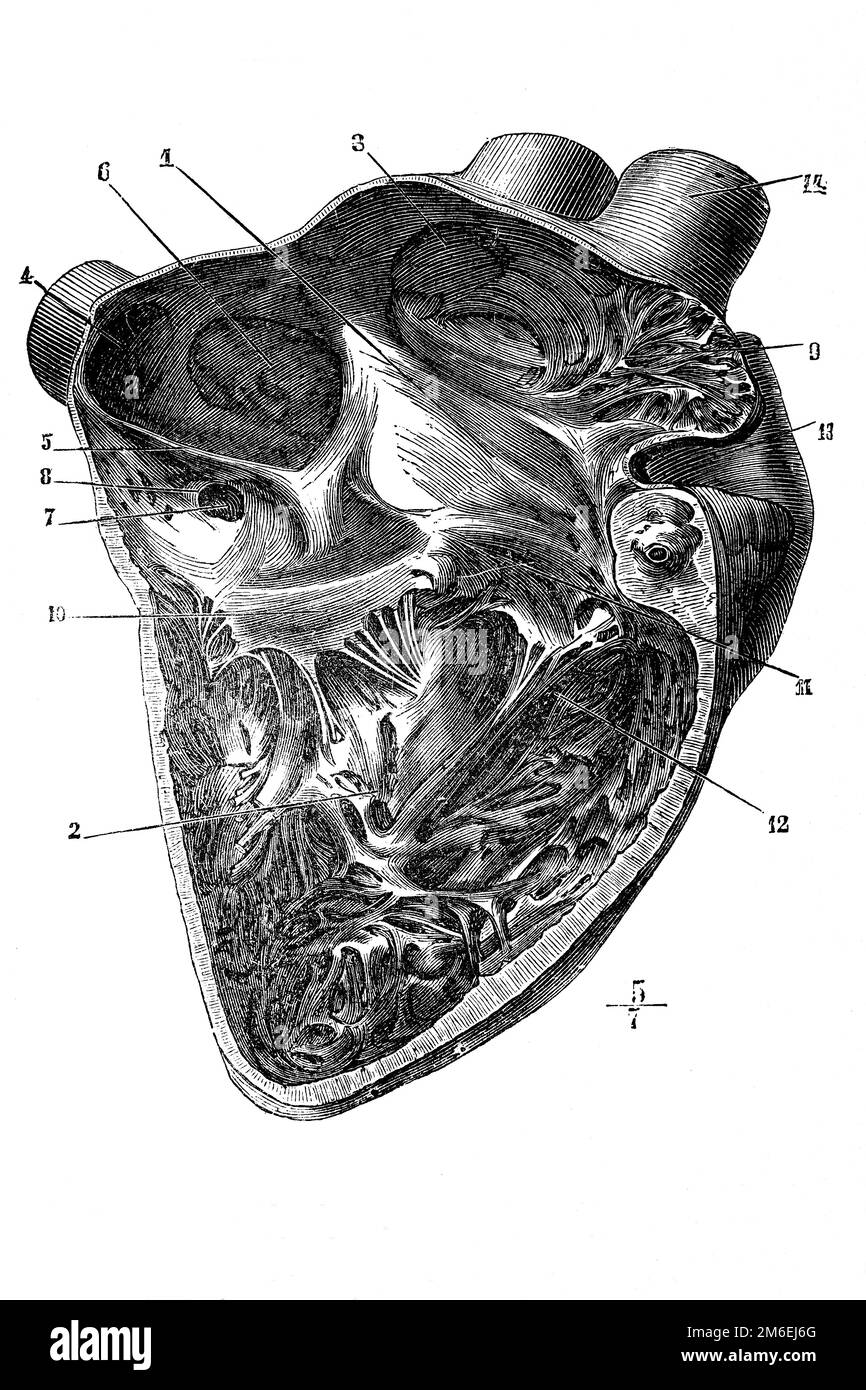

Sectional view of human heart. Antique illustration from a medical book. 1899. Stock Photohttps://www.alamy.com/image-license-details/?v=1https://www.alamy.com/sectional-view-of-human-heart-antique-illustration-from-a-medical-book-1899-image503110232.html

Sectional view of human heart. Antique illustration from a medical book. 1899. Stock Photohttps://www.alamy.com/image-license-details/?v=1https://www.alamy.com/sectional-view-of-human-heart-antique-illustration-from-a-medical-book-1899-image503110232.htmlRF2M6EJ6G–Sectional view of human heart. Antique illustration from a medical book. 1899.